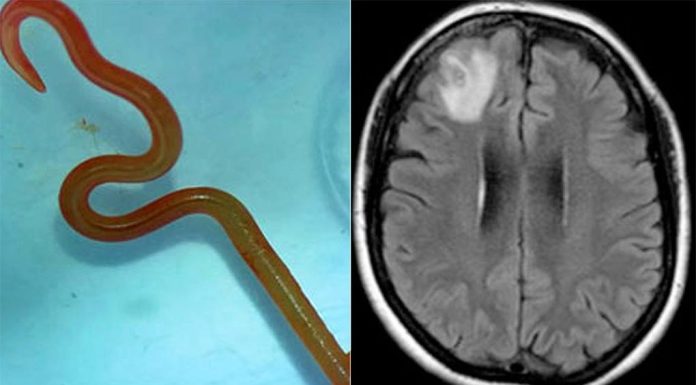

호주 의학 전문가들이 NSW 여성의 뇌 안에서 비단뱀(python snake)의 살아있는 8cm 길이의 회충을 발견했는데, 이는 세계 최초의 사례라고 9news가 전했다.

호주 국립 대학교(Australian National University)와 캔버라 병원(Canberra Hospital)에서 이 충격적인 사건에 대한 자세한 내용을 29일 발표했다. 64세 여성은 뇌 수술...